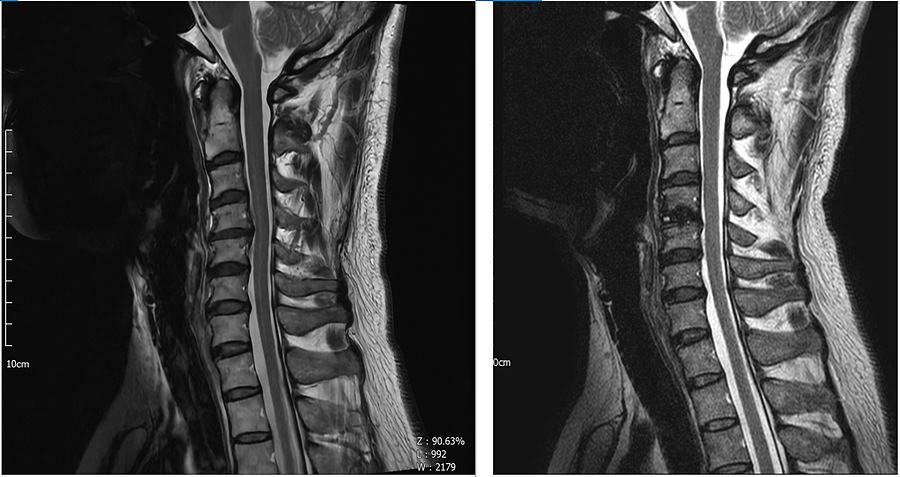

1. MRI 세로 사진 : 오른쪽이 수술후

. C4-C5부분이 약간의 역C자 였던 것도 정상 곡만?처럼 변경이 되었다.

. 교수님께서 앞에도 깍아냈다고 하심.

. 한순간에 이렇게 바뀌었는데 수술 후 극심한 통증을 겪는 것은 당연했다고 생각한다. 수술 후 공황장애같은 것도 겪고 극심한 통증도 겪었던 것들이 신경이 다시 셋업되는 과정이었다고 생각한다.